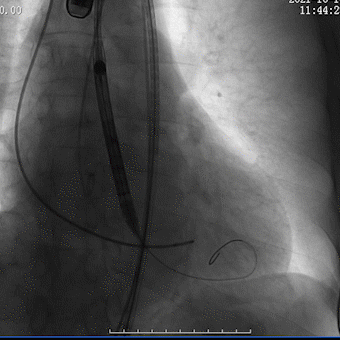

瓣膜回收调整位置

瓣膜再定位

瓣膜植入较深

瓣膜再回收调整